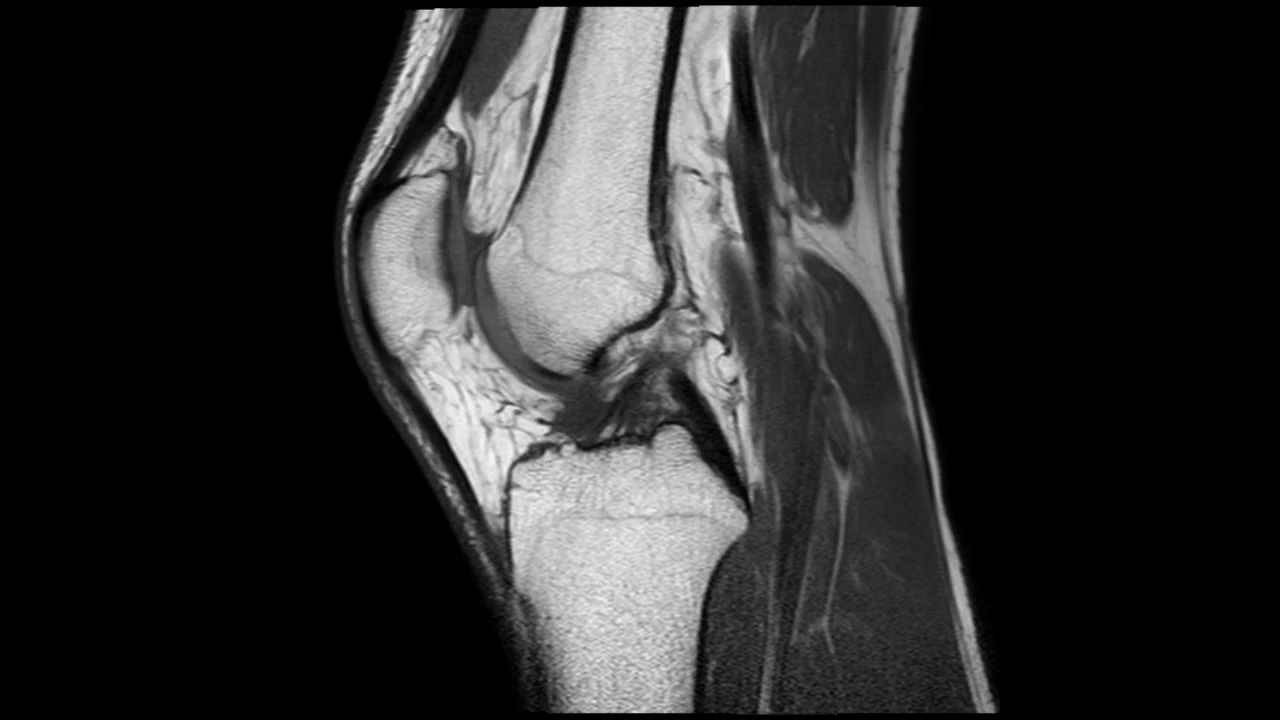

There are different types of radiology technology to see inside your body when you’re feeling poorly. There’s one type of radiology that uses powerful magnets to see inside our bodies. It’s called MRI!

MRI stands for Magnetic Resonance Imaging. Footballers with muscle injuries have these types of scan all the time.

- They’re also used for spine and brain injuries too because they’re very complex parts of the body and MRIs give the most detail of all.

MRI uses VERY strong magnets and radio frequency pulses to generate signals from the body. Every hydrogen atom in your body acts like a tiny magnet and an MRI scanner uses a huge magnet and radiowaves to generate signals from the hydrogen ions. The signals are detected by a radio antenna within the scanner and are processed by a computer to create really detailed images of the inside of your body.